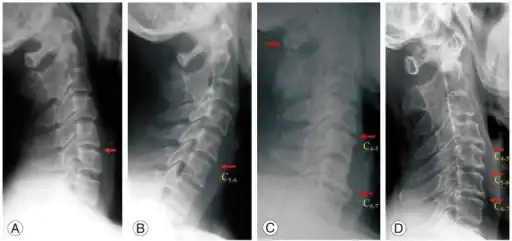

a,b) Mono segment spondylosis at C5-6 c) Two-segment spondylosis at C4-5 and C6-7 d) Three-segment spondylosis at C4-5, C5-6, and C6-7 -